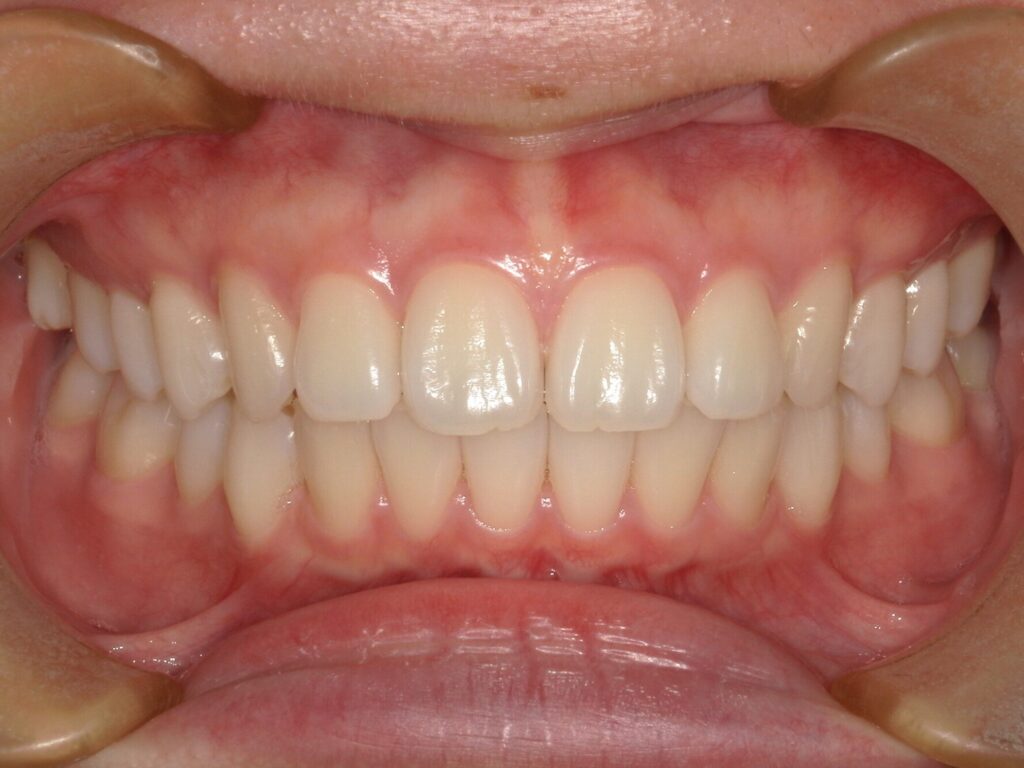

【A様】

Before

After

年齢 | 20代前半 |

性別 | 女性 |

主訴 | 上下の前歯が前に出ている。かみ合わせが悪く、食いしばりをしていて、頬の粘膜に傷ができやすい。 |

施術内容 | アライナー(マウスピース)矯正 |

治療期間 | 10ヶ月 |